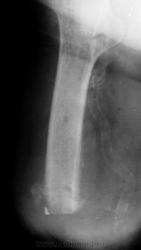

Помогите интерпретировать снимки. Женщине 73 года, в августе 2010 ампутация по поводу гангрены стопы, сахарный диабет. Около недели гнойное отделяемое из рубца, со слов.

В приёмном отделении, местный статус: отёка культи нет; свищ в области постеоперационного рубца, на момент осмотра отделяемого нет; гиперемии кожи культи нет.

Осмотр хирурга гнойного отделения: состояние удовлетворительное. В области п/о рубца участок гипергрануляции 0.5х0.5 см, отёка культи нет. Рубец - без признаков воспаления.

Поступила сегодня, результатов анализов еще нет. Поставила остеомиелит, но у меня впечатление, что на спил одет какой-то колпачок, но я ни разу такого не видела. Может, кому встречалось подобное?

Остеомиелит дистального конца культи.

ничего не имею против остеомиелита. Я его и поставила. Мне не ясен четкий, как по линеечке, ровный нижний контур и треугольная плотная тень с ровными контурами по наружному краю. Применяется ли какой-то колпачок на спил? Потому что у меня сомнение, что на самом дистальном краю - именно костная ткань...

А знаете, отторгнутый дистальный "эпифиз" и может быть целым секвестром.

Читаем Рейнберга: "Наиболее типичными для культи являются так называемые венечные, коронарные секвестры (рис. 115). Венечный остеонекроз имеет вид кольца или в более редких случаях - довольно высокого цилиндра. Он охватывает то всю кость по окружности, то только часть диафизарного цилиндра. Иногда венечный остеонекроз имеет форму воронки, образующейся из внутренних или внешних слоев коркового вещества."

Можете посмотреть http://v-ugnivenko.narod.ru/Rh/2-4.html - один в один

Коллега, или я чего-нибудь не понял или ошибка вкралась, но вы писали, что была ампутация стопы, а видим культю бедра(?)...

"...в августе 2010 ампутация на уровне средней трети бедра по поводу гангрены стопы, сахарный диабет" - пропустила в начале ветки.